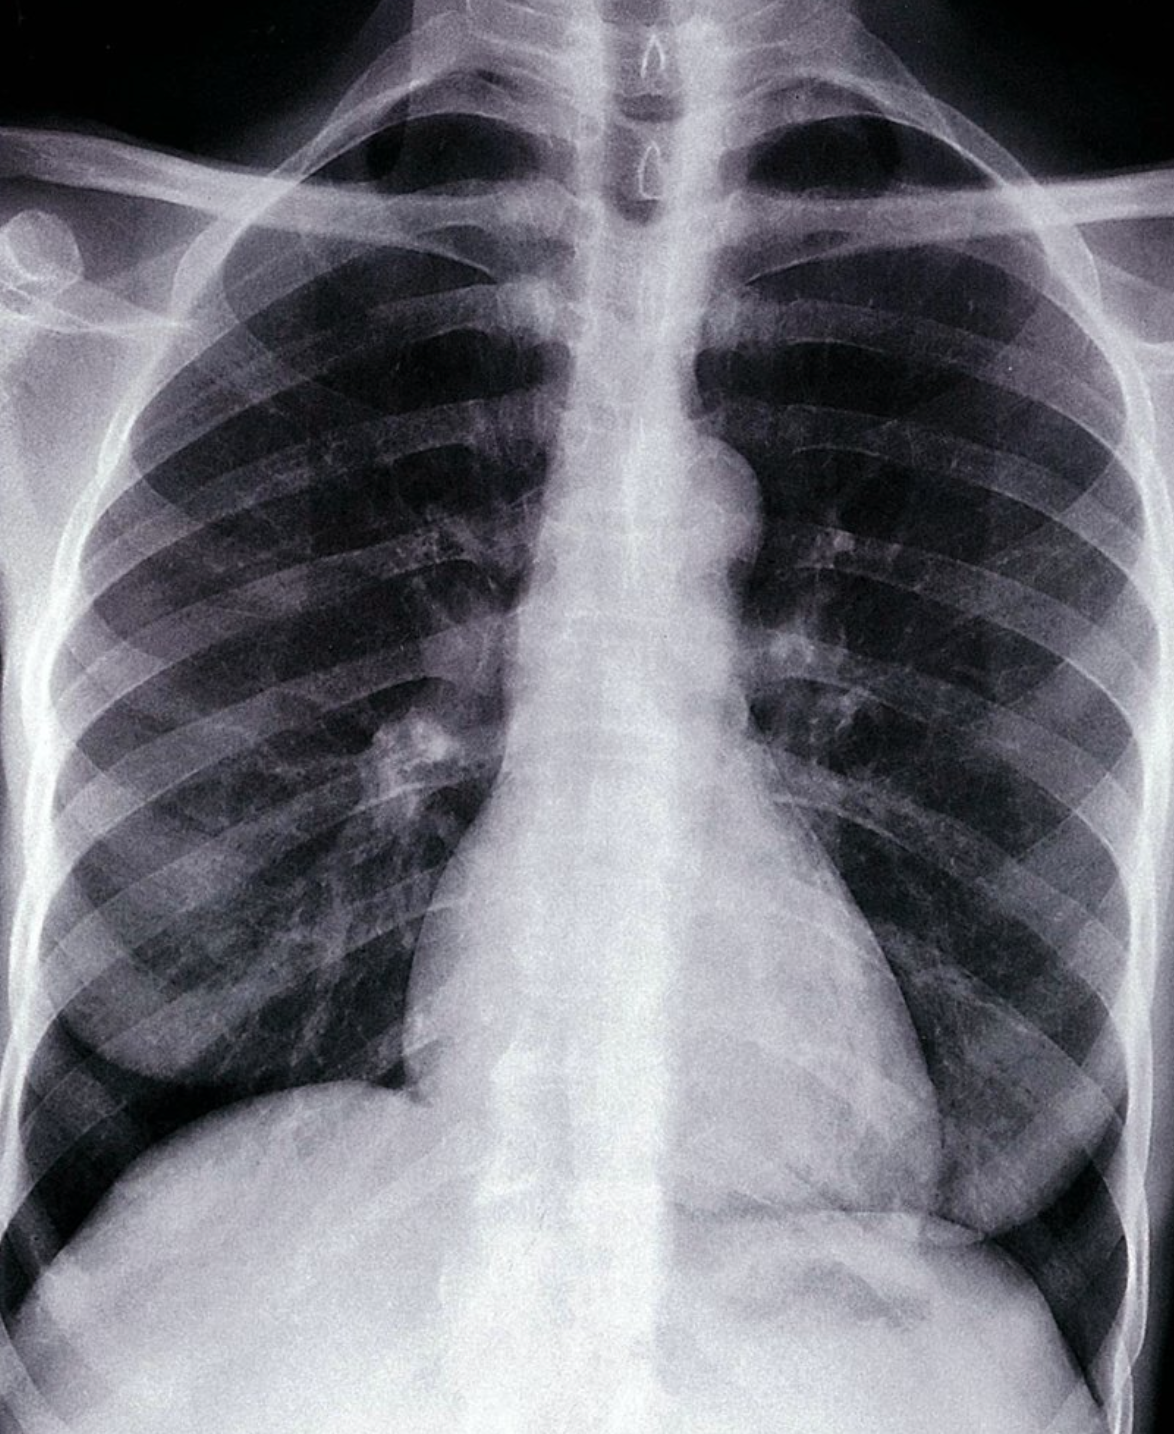

Elevation of the left hemidiaphragm with left basal atelectasis

Chest x-ray (PA view)

There is basal atelectasis of the left lung with elevation of the left hemidiaphragm. The colon (hatched overlay) is filled with air and there is a mediastinal shift to the right (arrows). A round, possibly neoplastic lesion (circle) is visible in the lower zone of the right lung